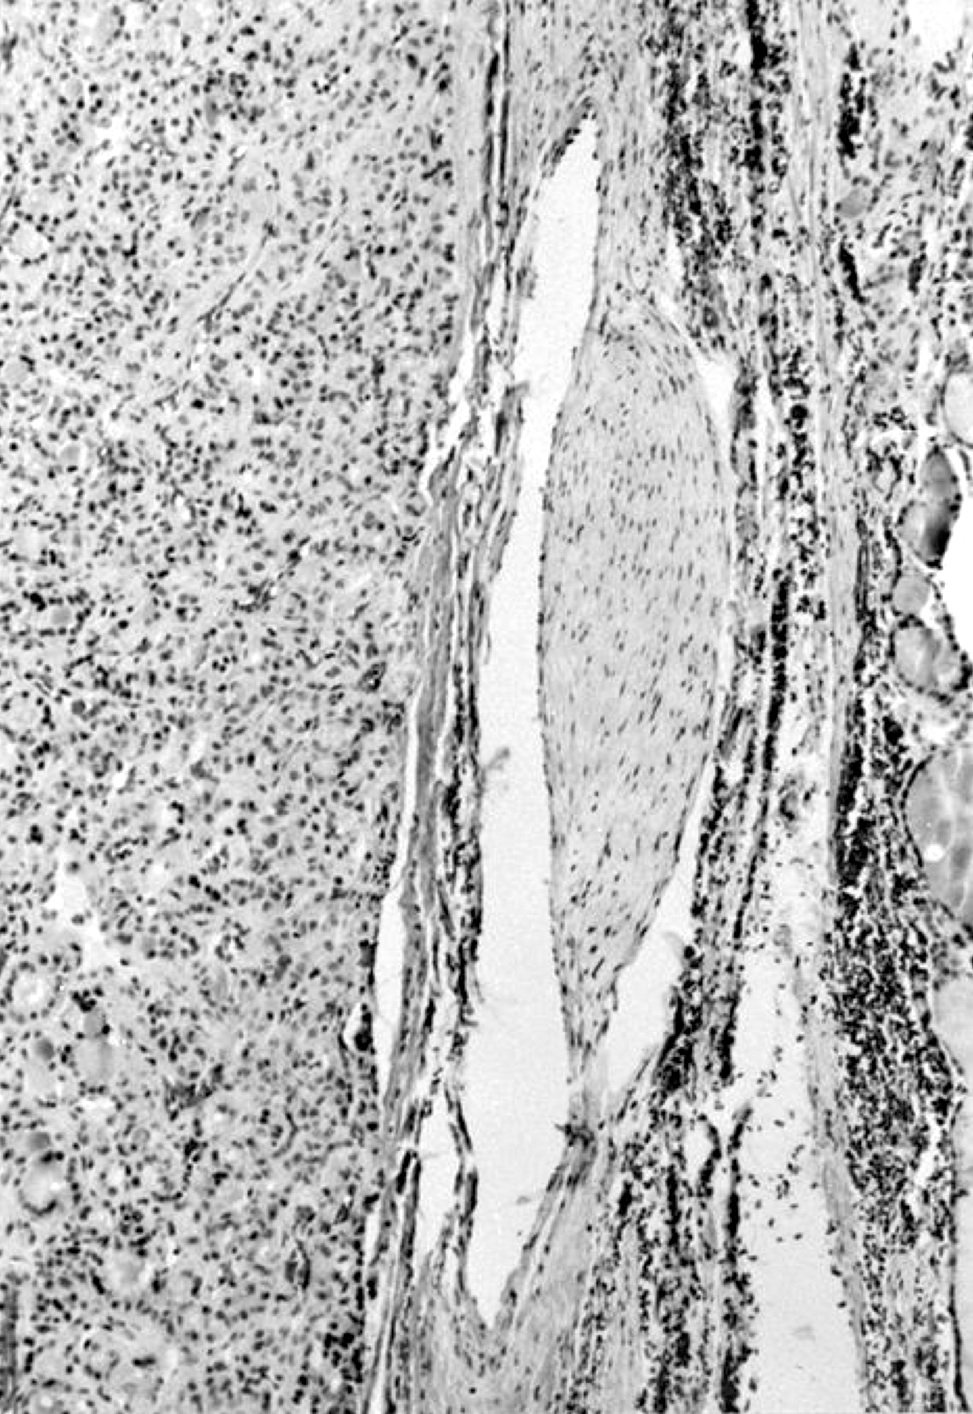

Microscopic (histologic) description

- Encapsulated; thin or moderately thick capsule

- Secondary changes: fibrosis, hyalinization, hemorrhage, hemosiderin deposition, edema, cystic degeneration, calcification, osseous or cartilaginous metaplasia

- No capsular or vascular invasion after thorough sampling (at least 10 blocks)

Microscopic (histologic) images

Contributed by Shipra Agarwal, M.D., Andrey Bychkov, M.D., Ph.D., Mark R. Wick, M.D., Asmaa Gaber Abdou, M.D. and AFIP

Atypical adenomas:

Not invasion: